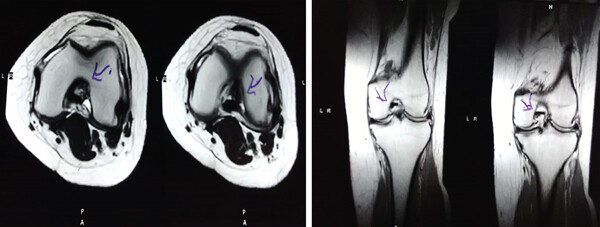

影像學(xué)檢查:4例MM皮瓣撕裂患者在治療前后交界區(qū)中央?yún)^(qū)域出現(xiàn)缺損,但其中2例患者該區(qū)域完全恢復(fù)穩(wěn)定光滑狀態(tài),另2例患者該區(qū)域部分恢復(fù)。治療前后交界區(qū)中央?yún)^(qū)域皮瓣撕裂的關(guān)節(jié)鏡評分為0.3±0.5,治療后為4.3±2.1,治療后評分顯著升高。2例患者原有放射狀MM撕裂在治療一年后愈合。

關(guān)節(jié)功能:治療后4周和52周的Lysholm評分顯著高于治療前。

結(jié)論:間充質(zhì)干細胞移植后,隨訪24個月內(nèi),患者影像學(xué)和關(guān)節(jié)功能顯著改善,未發(fā)生嚴(yán)重不良事件。可以達到干細胞治療半月板損傷長期療效的目標(biāo)。